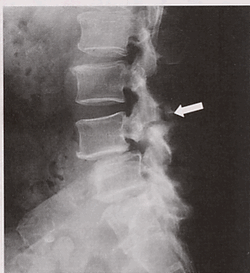

脊柱管狭窄症やすべり症と診断された方は、病院の先生からレントゲンやMRIの画像を見て、

腰椎のレントゲン画像。すべり症が疑われる部分を矢印で示した図

• 「神経が圧迫を受けている」

• 「脊柱管が狭くなっている」

• 「骨がすり減っている」

と、いう説明を受けるケースがほとんど。